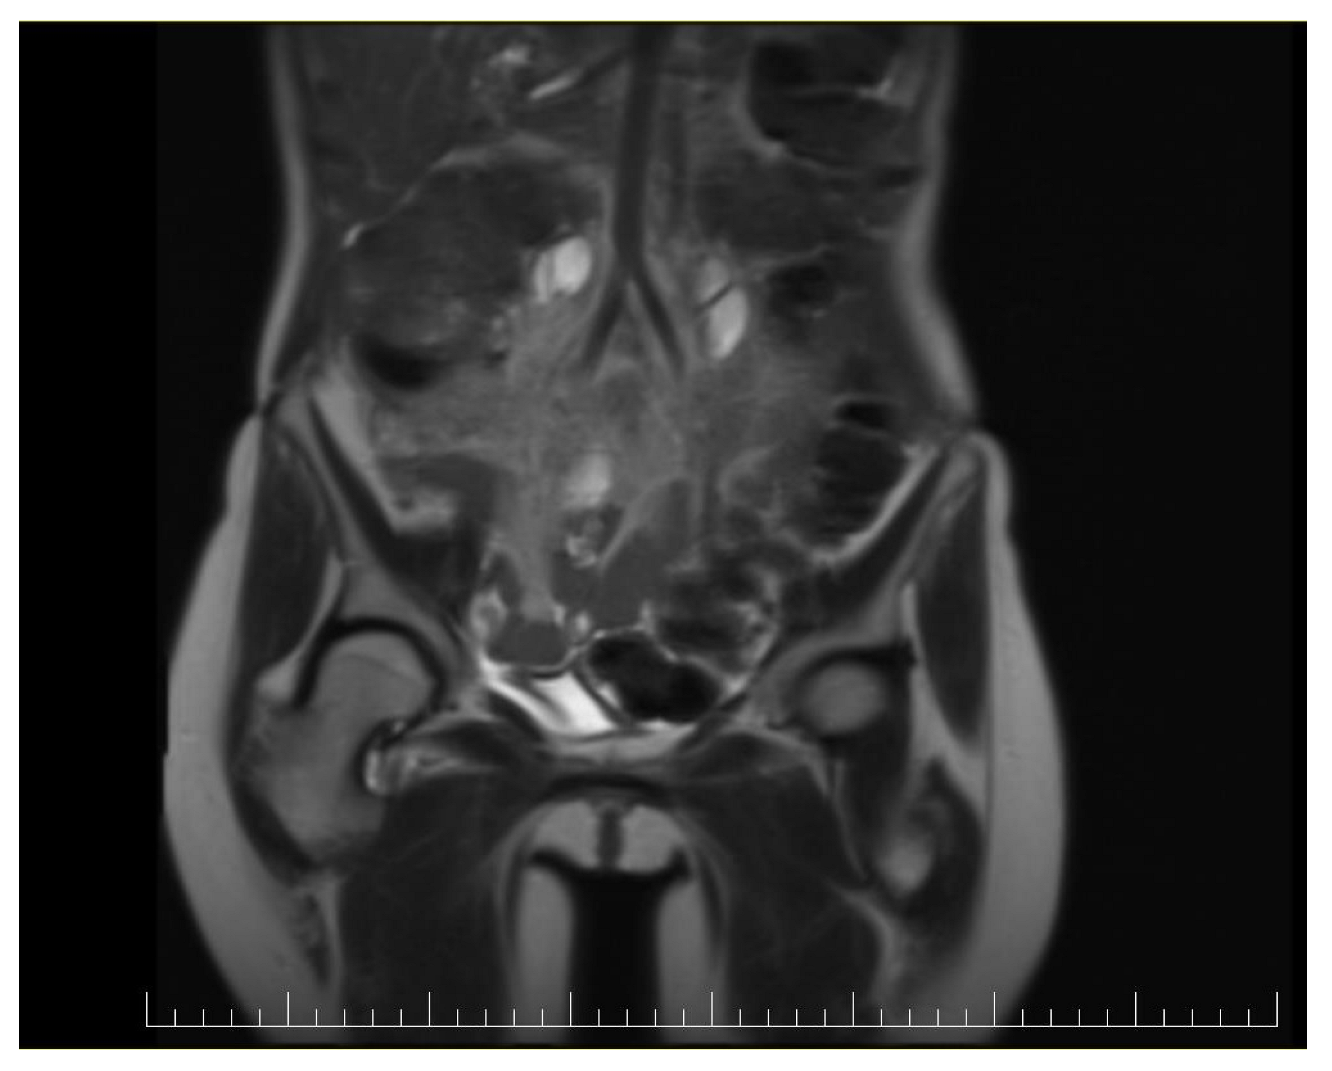

This case report details the presentation, diagnosis, and management of a 44-year-old female who experienced a relapse of colonic cancer with peritoneal carcinomatosis in 2021, two years after the initial diagnosis. The patient exhibited specific symptoms indicative of disease recurrence. In 2019, the patient underwent surgical resection and received adjuvant chemotherapy for colonic cancer. Despite an initial period of remission, in 2021 she presented with symptoms such as abdominal distension, persistent abdominal pain, and changes in bowel habits. Imaging studies, including CT scans, confirmed the presence of peritoneal carcinomatosis, indicating a relapse of colonic cancer along with two suspected tumorous formations localized in the ovaries (Figure 1 and Figure 2). Upon relapse, the patient underwent a thorough diagnostic workup, including imaging studies and tumor marker assessments. Elevated levels of carcinoembryonic antigen (CEA) of 5.44 ng/mL and CA-19-9 of 58 U/mL were observed, supporting the diagnosis of colonic cancer recurrence with peritoneal carcinomatosis.

Figure 1.

Preoperatory coronal view of a Computed Tomography (CT) image presenting a giant ovarian mass.

Figure 2.

Preoperatory sagittal view of a CT image presenting a giant ovarian mass.